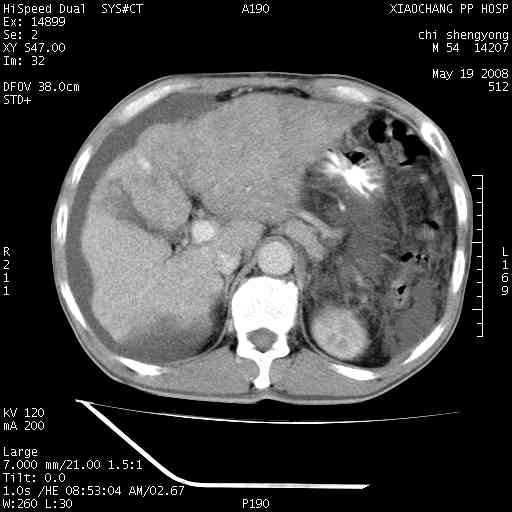

以下是引用zjzjr在2008-5-21 10:52:00的发言:[br]肝左叶巨块型肝癌伴门静脉左支瘤栓形成.肝硬化、腹水,胃底静脉曲张,脾术后改变。

以下是引用随光逐影在2008-5-21 16:20:00的发言:[br]1)肝左叶肝癌伴门静脉左支瘤栓形成,腹膜后淋巴结转移。2)肝硬化、腹水、胃底静脉曲张。3)胆囊炎。4)脾脏缺如,为切除术后所致。